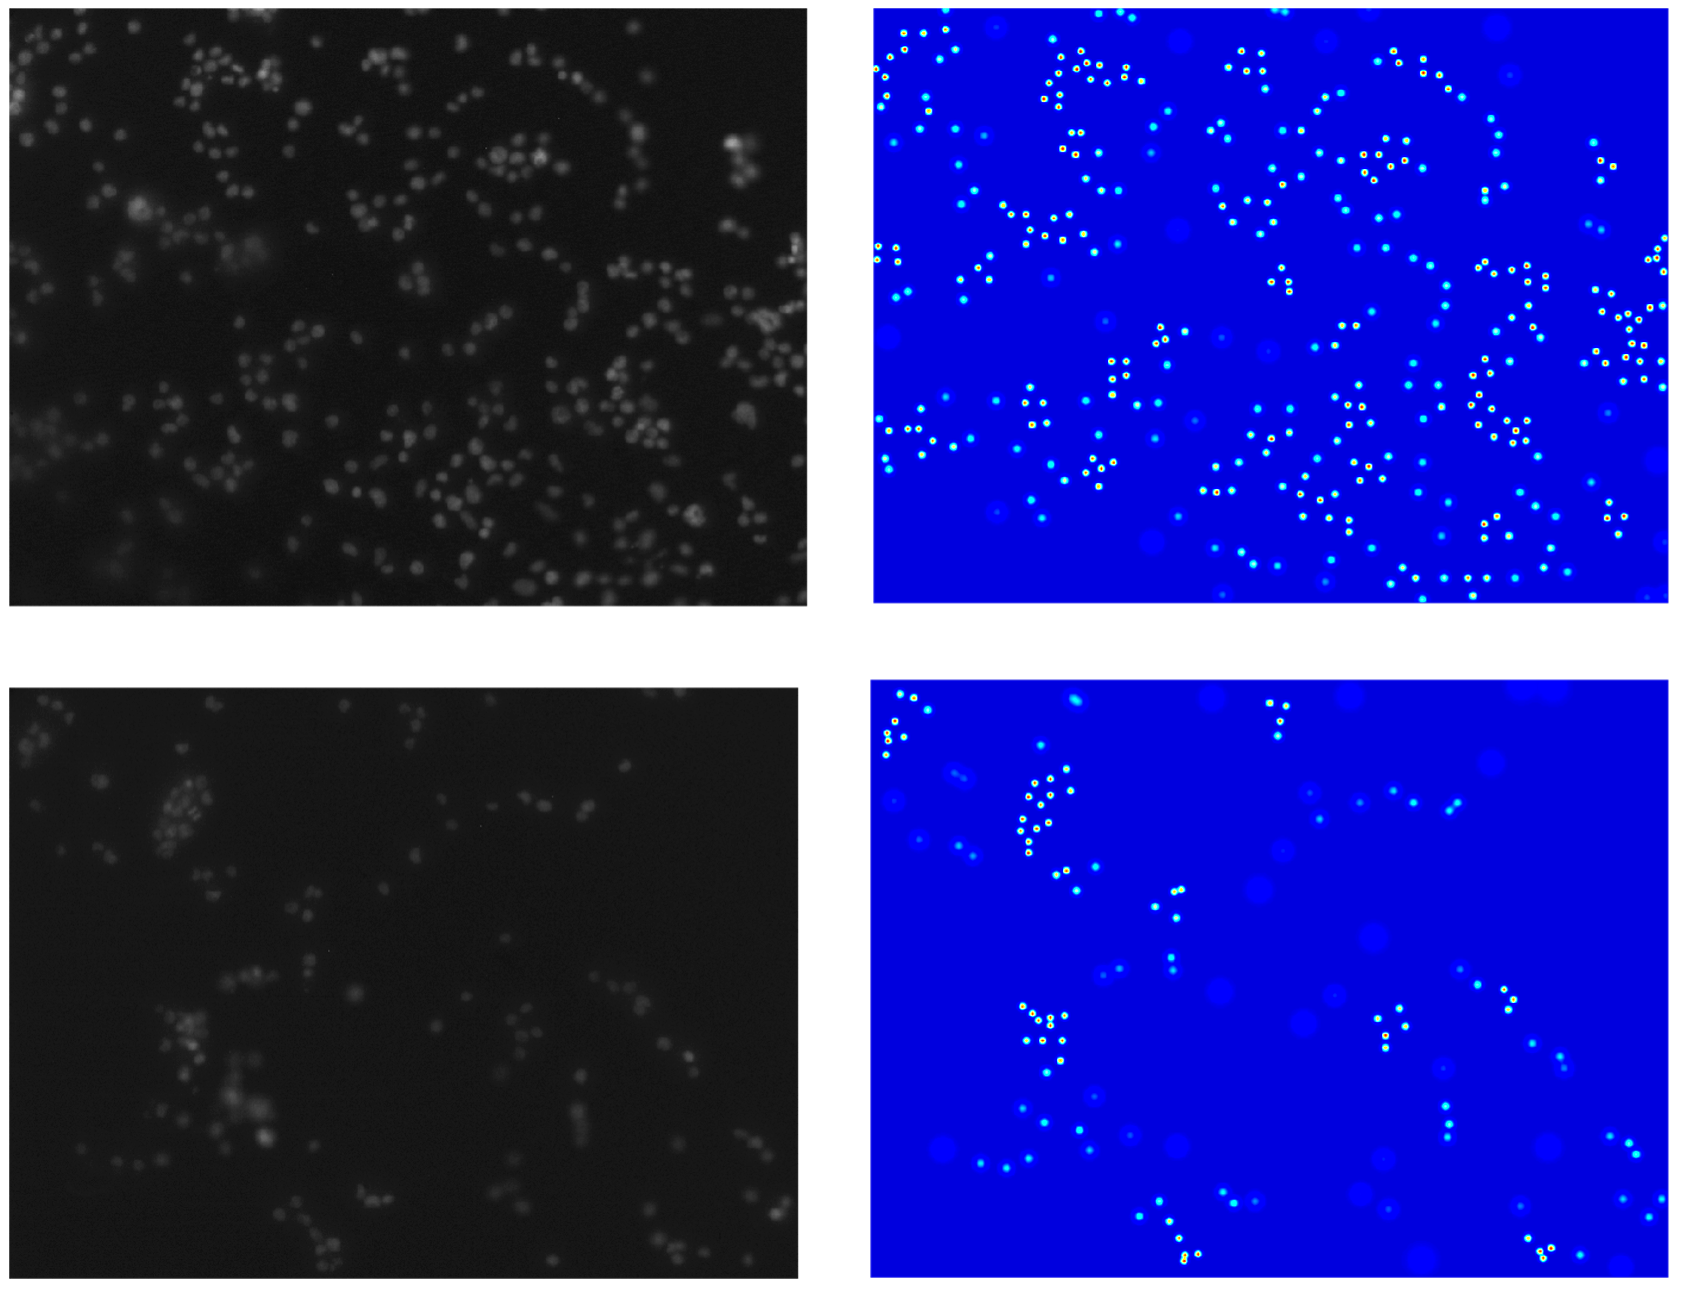

CSRNet (Li et al., 2018) and MCNN (Zhang et al., 2016) are density-map based models developed for counting people in a congested environment. These models can handle dense crowds, which makes them well-suited for handling cell congestion. In addition, these models were designed to be robust to variations in object size and shape, lighting, and contrast conditions. CSRNet is a two-component network with a CNN as the first component for feature extraction. The second component is a dilated CNN to produce larger reception fields, replacing pooling operations. MCNN extracts scale-relevant features by using filters with different sizes of receptive fields. The authors proposed a network of three parallel CNNs with different filter sizes. For an input image, the network averages the predicted density maps of the three CNNs and outputs a final count prediction. To use the dot-annotated images for training CSRNet and MCNN, we followed the ground truth generation method in (Zhang et al., 2016) by blurring each dot annotation using a Gaussian kernel to produce corresponding density maps. Since the generated density maps have a high impact on the performance of the models for cell counting, we used geometry-adaptive kernels (Li et al., 2018) to accurately generate corresponding density maps for input images. Fig. 3 (left) shows input images. Fig. 3 (right) shows the corresponding density maps generated.

images on the left and Density maps on the right